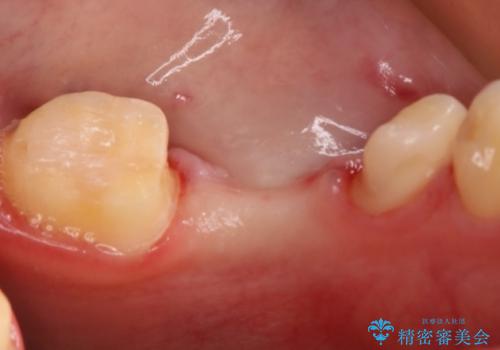

支台歯部分はインレー形態でしたが強度や維持性を考慮しクラウン形態への変更を計画しました。

後ろの歯が前に倒れ込んでいましたが問題なく治療を終えることが出来ました。